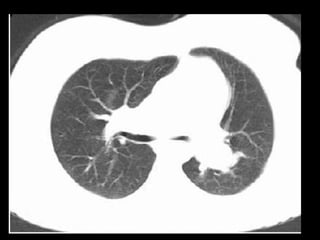

TC normal de tórax